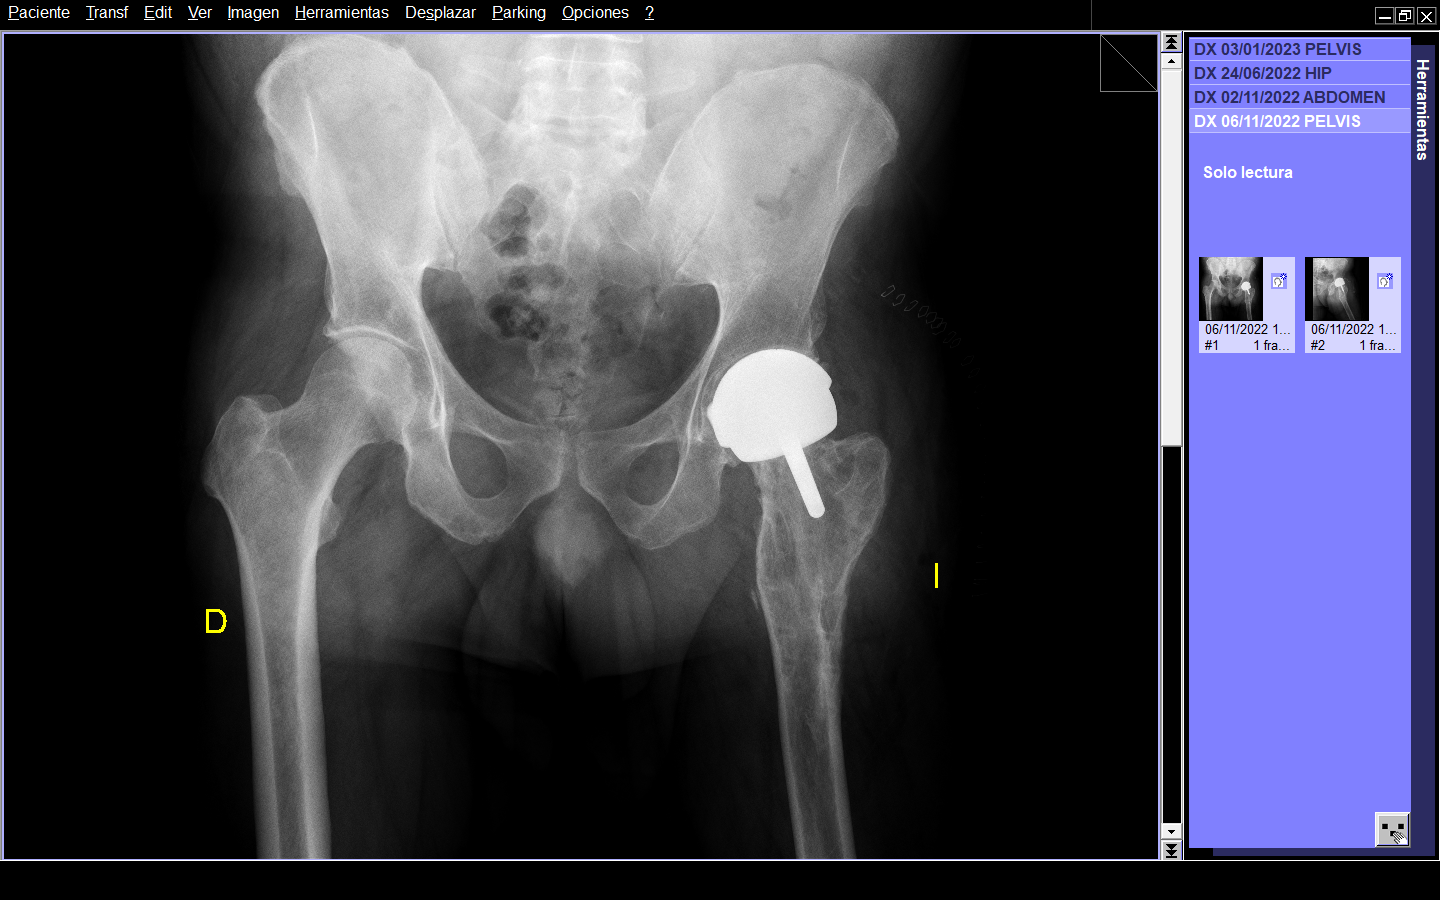

Radiográficamente, en AP presentaba deformidad en fémur proximal izquierdo de 160º en valgo, disminución del espacio articular, geodas en cabeza femoral. En la radiografía lateral se observaba curvatura en la metáfisis femoral con ápex posterior de 27º. (Figura 1 y 2)

Figura 1. Radiografía AP de ambas caderas.